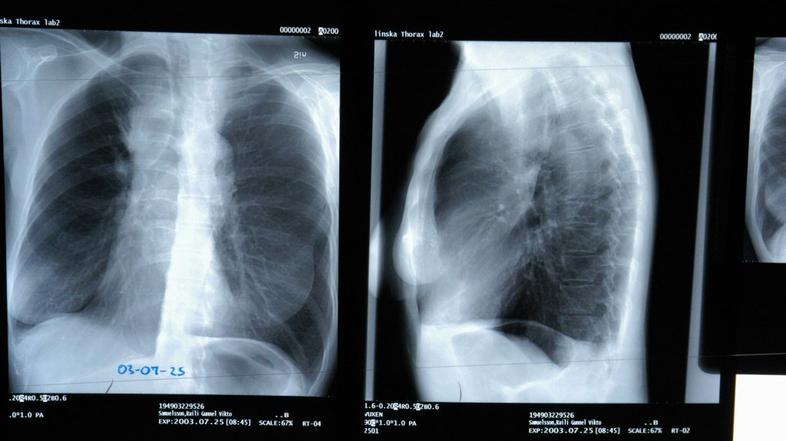

Pljučni rak Profimedias

Rak pljuč je najpogostejša oblika raka. Vsako leto ga odkrijejo pri okoli 1.8 milijonih ljudi, okoli 1.6 milijona jih letno umre zaradi te bolezni.

Podatki kažejo, da je leta 2012 v Sloveniji zaradi pljučnega raka zbolelo 1260 oseb, v istem letu pa jih je umrlo 1131.